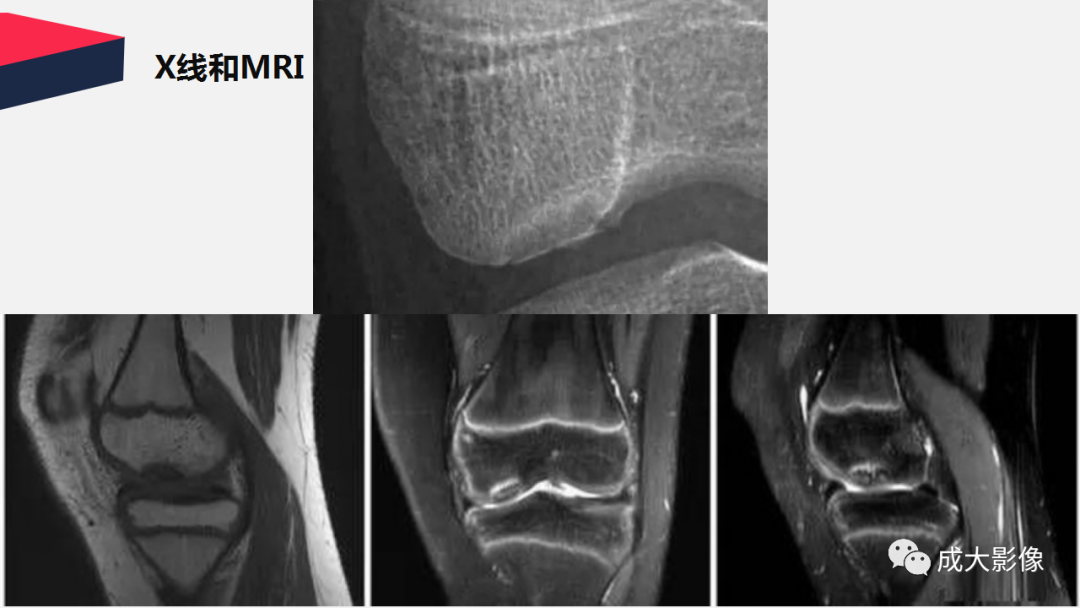

【PPT】剥脱性骨软骨炎-2